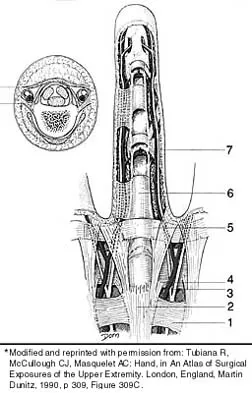

Question 95

Which of the following anatomic structures is labeled 6 in Figure 27?

Explanation